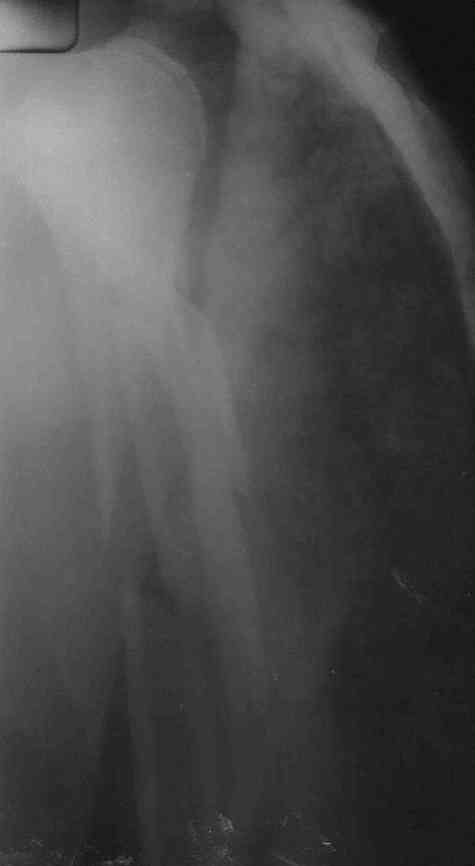

Re: Многооскольчатый перелом плечевой кости в В/3

Немножко переделал повязку с отведением, подправил, вот что получилось.

Перелом внутрисуставной, Вы уверены на счет Сармиенто? На первичном снимке не видно было перелома головки.

В наших условиях выбрали бы закрытое штифтование проксимальным гвоздем для плеча T2 Stryker. Голоку предварительно бы фиксировали спицами вне траектории гвоздя, чтобы не разобщить отломки.